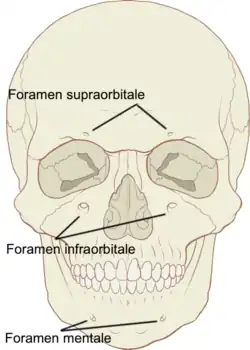

Durch das Setzen eines weiteren kleinen Depots von etwa 0,3 ml des Anästhetikums wird in etwa 10 mm Abstand vom Knochen am aufsteigenden Ast des Unterkiefers der Nervus lingualis anästhesiert. Zur Anästhesie des Nervus buccalis werden entweder in der Umschlagfalte des Mundvorhofes vestibulär im Bereich des zu behandelnden Zahnes oder am medialen Rand des aufsteigenden Unterkieferastes 0,3 ml des Anästhetikums injiziert. Zur Ausschaltung der Anastomosen wird bei Bedarf der Nervus mentalis am Foramen mentale anästhesiert.

| Leitungsanästhesie des Nervus mentalis (V3) | Schleimhaut, Haut und Muskel im Kinnbereich einer Seite |

| Extraorale Leitungsanästhesie des Nervus mentalis (V3) | dto. |

| Extraorale Leitungsanästhesie des Nervus infraorbitalis (V2) | über die Rami alveolares alle Zähne einer Oberkieferhälfte und die Haut einer vorderen und oberen Gesichtshälfte |

Nervus mentalis

In ebenfalls sehr seltenen Fällen kann eine extraorale Leitungsanästhesie des Nervus mentalis durchgeführt werden. Hierzu wird die Einstichstelle drei Zentimeter unterhalb des Mundwinkels aufgesucht. Die Injektionskanüle wird senkrecht bis zum Knochenkontakt eingeführt.

Nervus infraorbitalis

Bei der extraoralen Technik zur Leitungsanästhesie des Nervus infraorbitalis markiert man durch Palpation mit dem Zeigefinger der linken Hand von außen die Gegend des Foramen infraorbitale und sticht die Kanüle unterhalb des markierenden Fingers durch die Haut in Richtung auf das Foramen infraorbitale ein. Eine Injektion in den Canalis infraorbitalis ist zu vermeiden, da sonst eine Nervschädigung mit langandauernden Beschwerden nicht ausgeschlossen werden kann.[55]